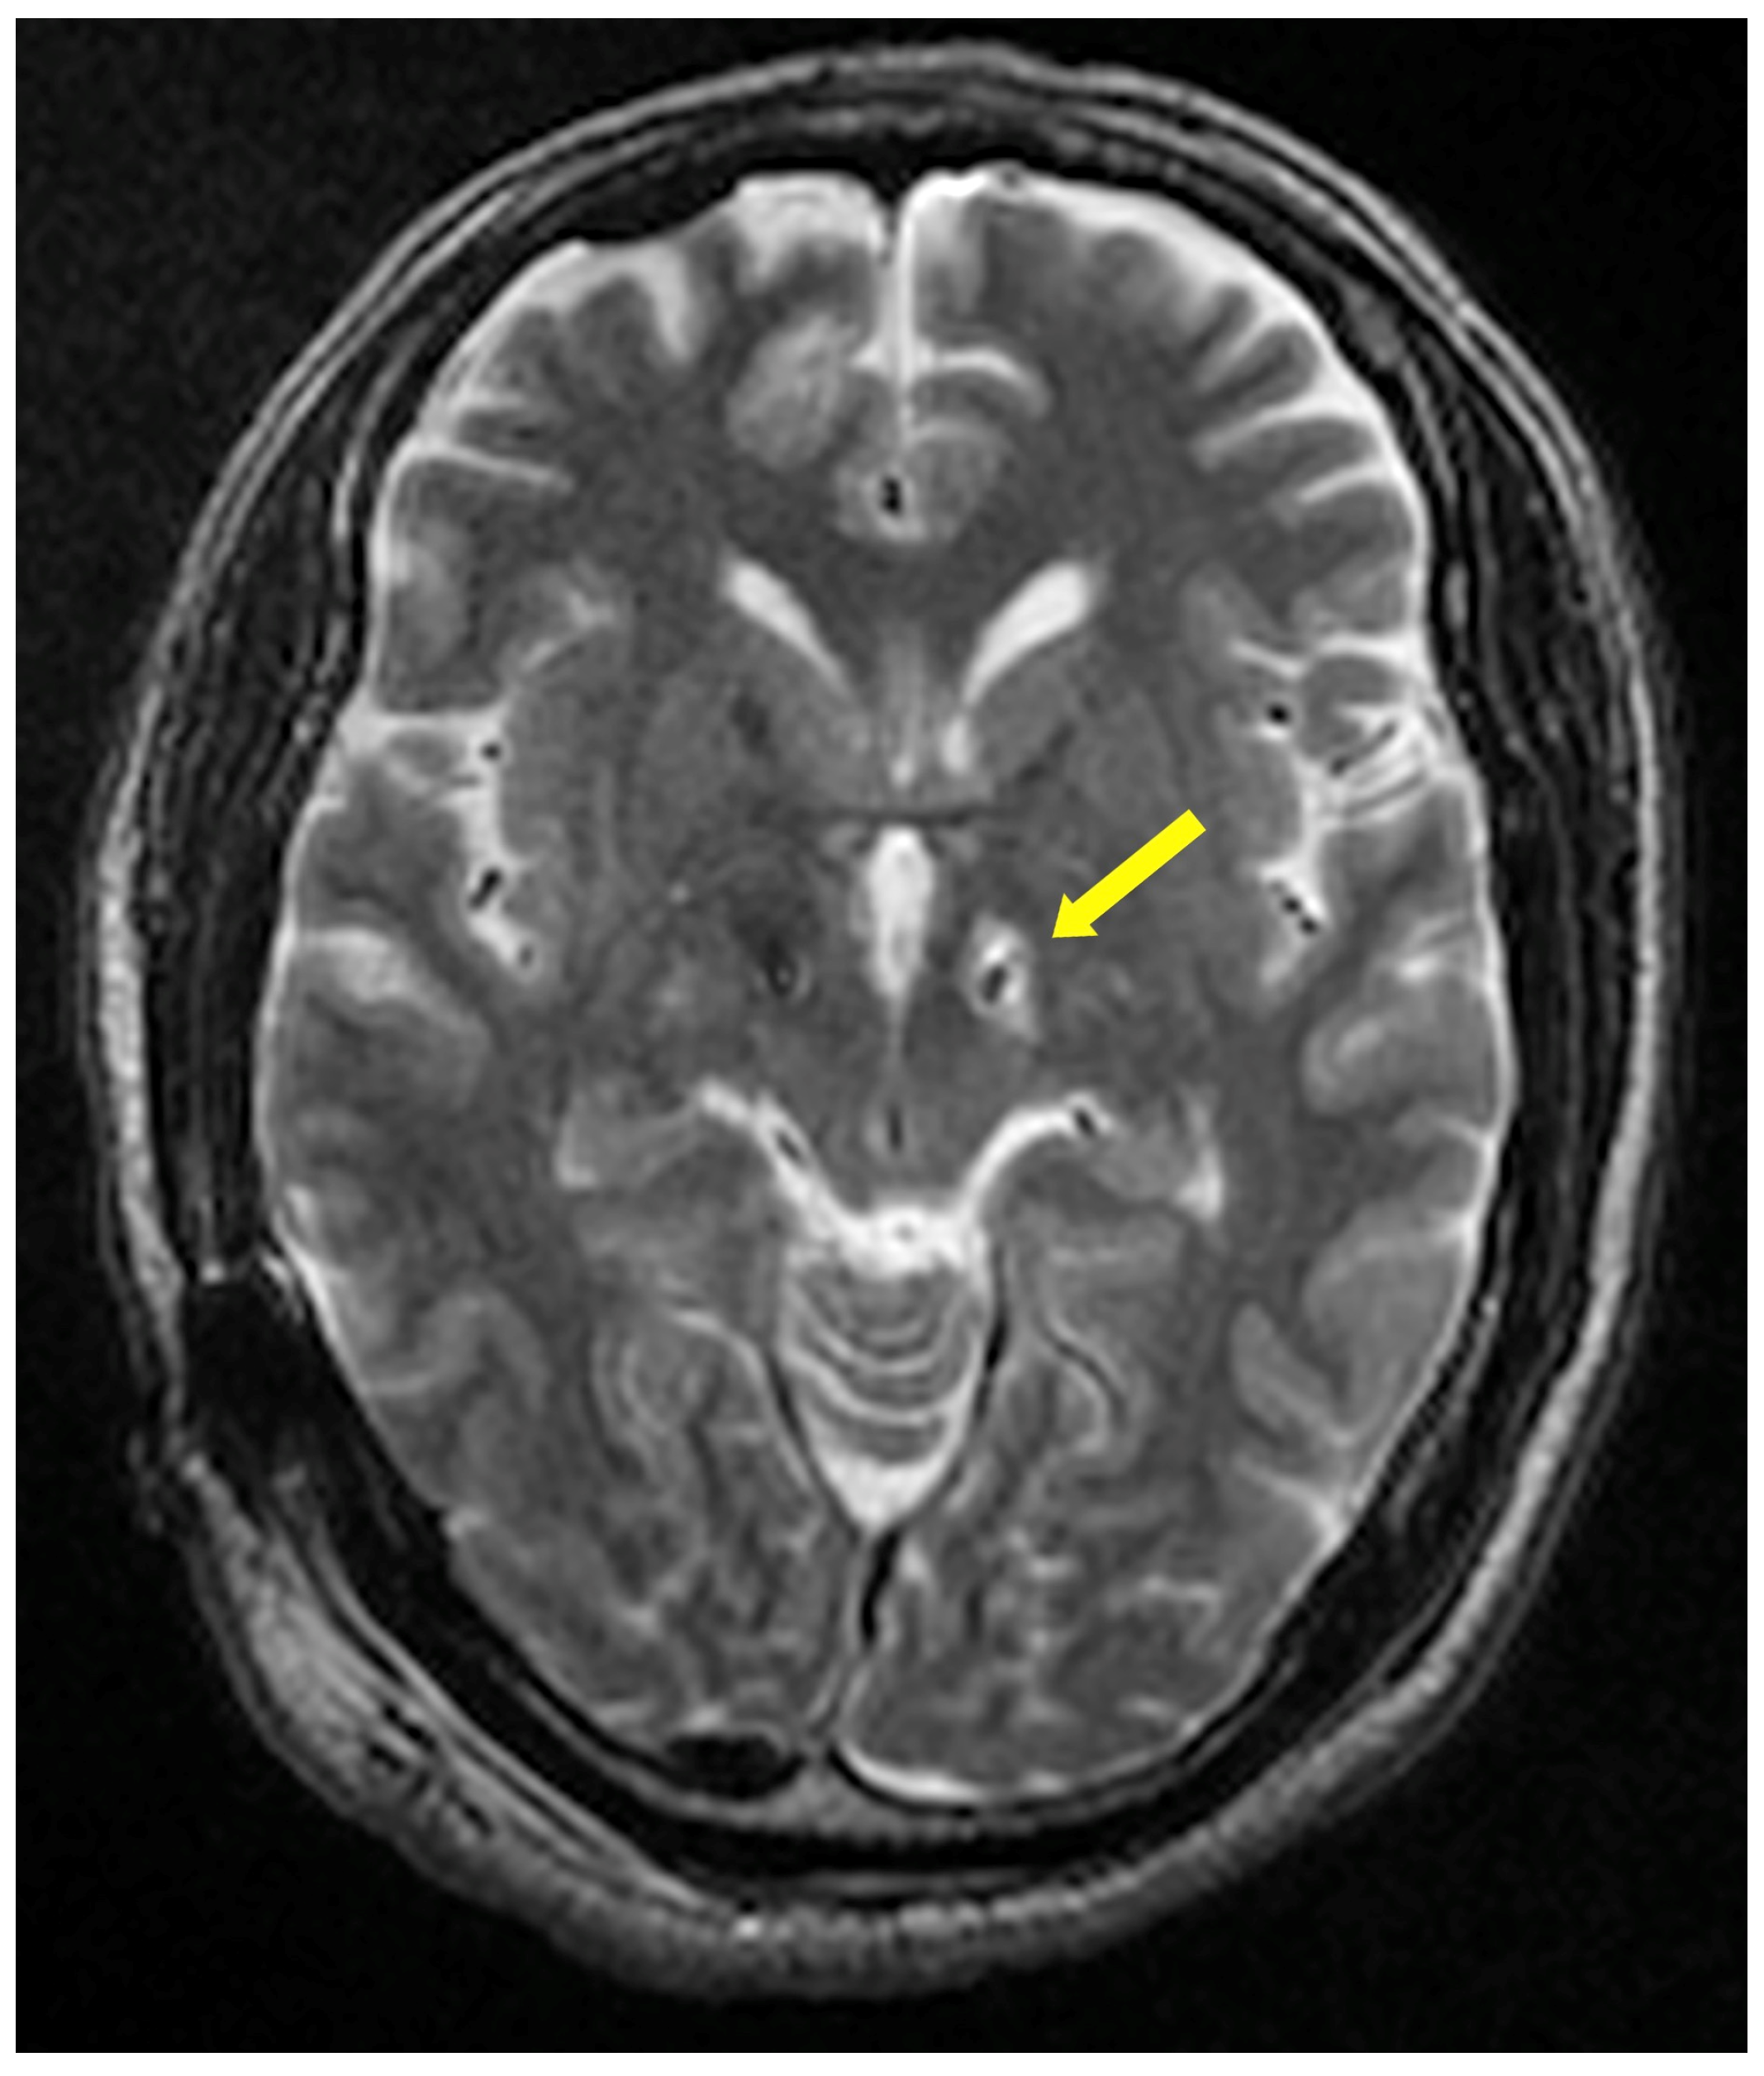

| Limited peri-electrode edema on T2 | 145 (75.92) | 121 (70.07) | 32 (94.12) | 0.04 |

| Limited peri-electrode edema on T2 | 4.76 | 1.09 | 20.8 | 0.04 | 7.63 | 1.37 | 42.37 | 0.02 |